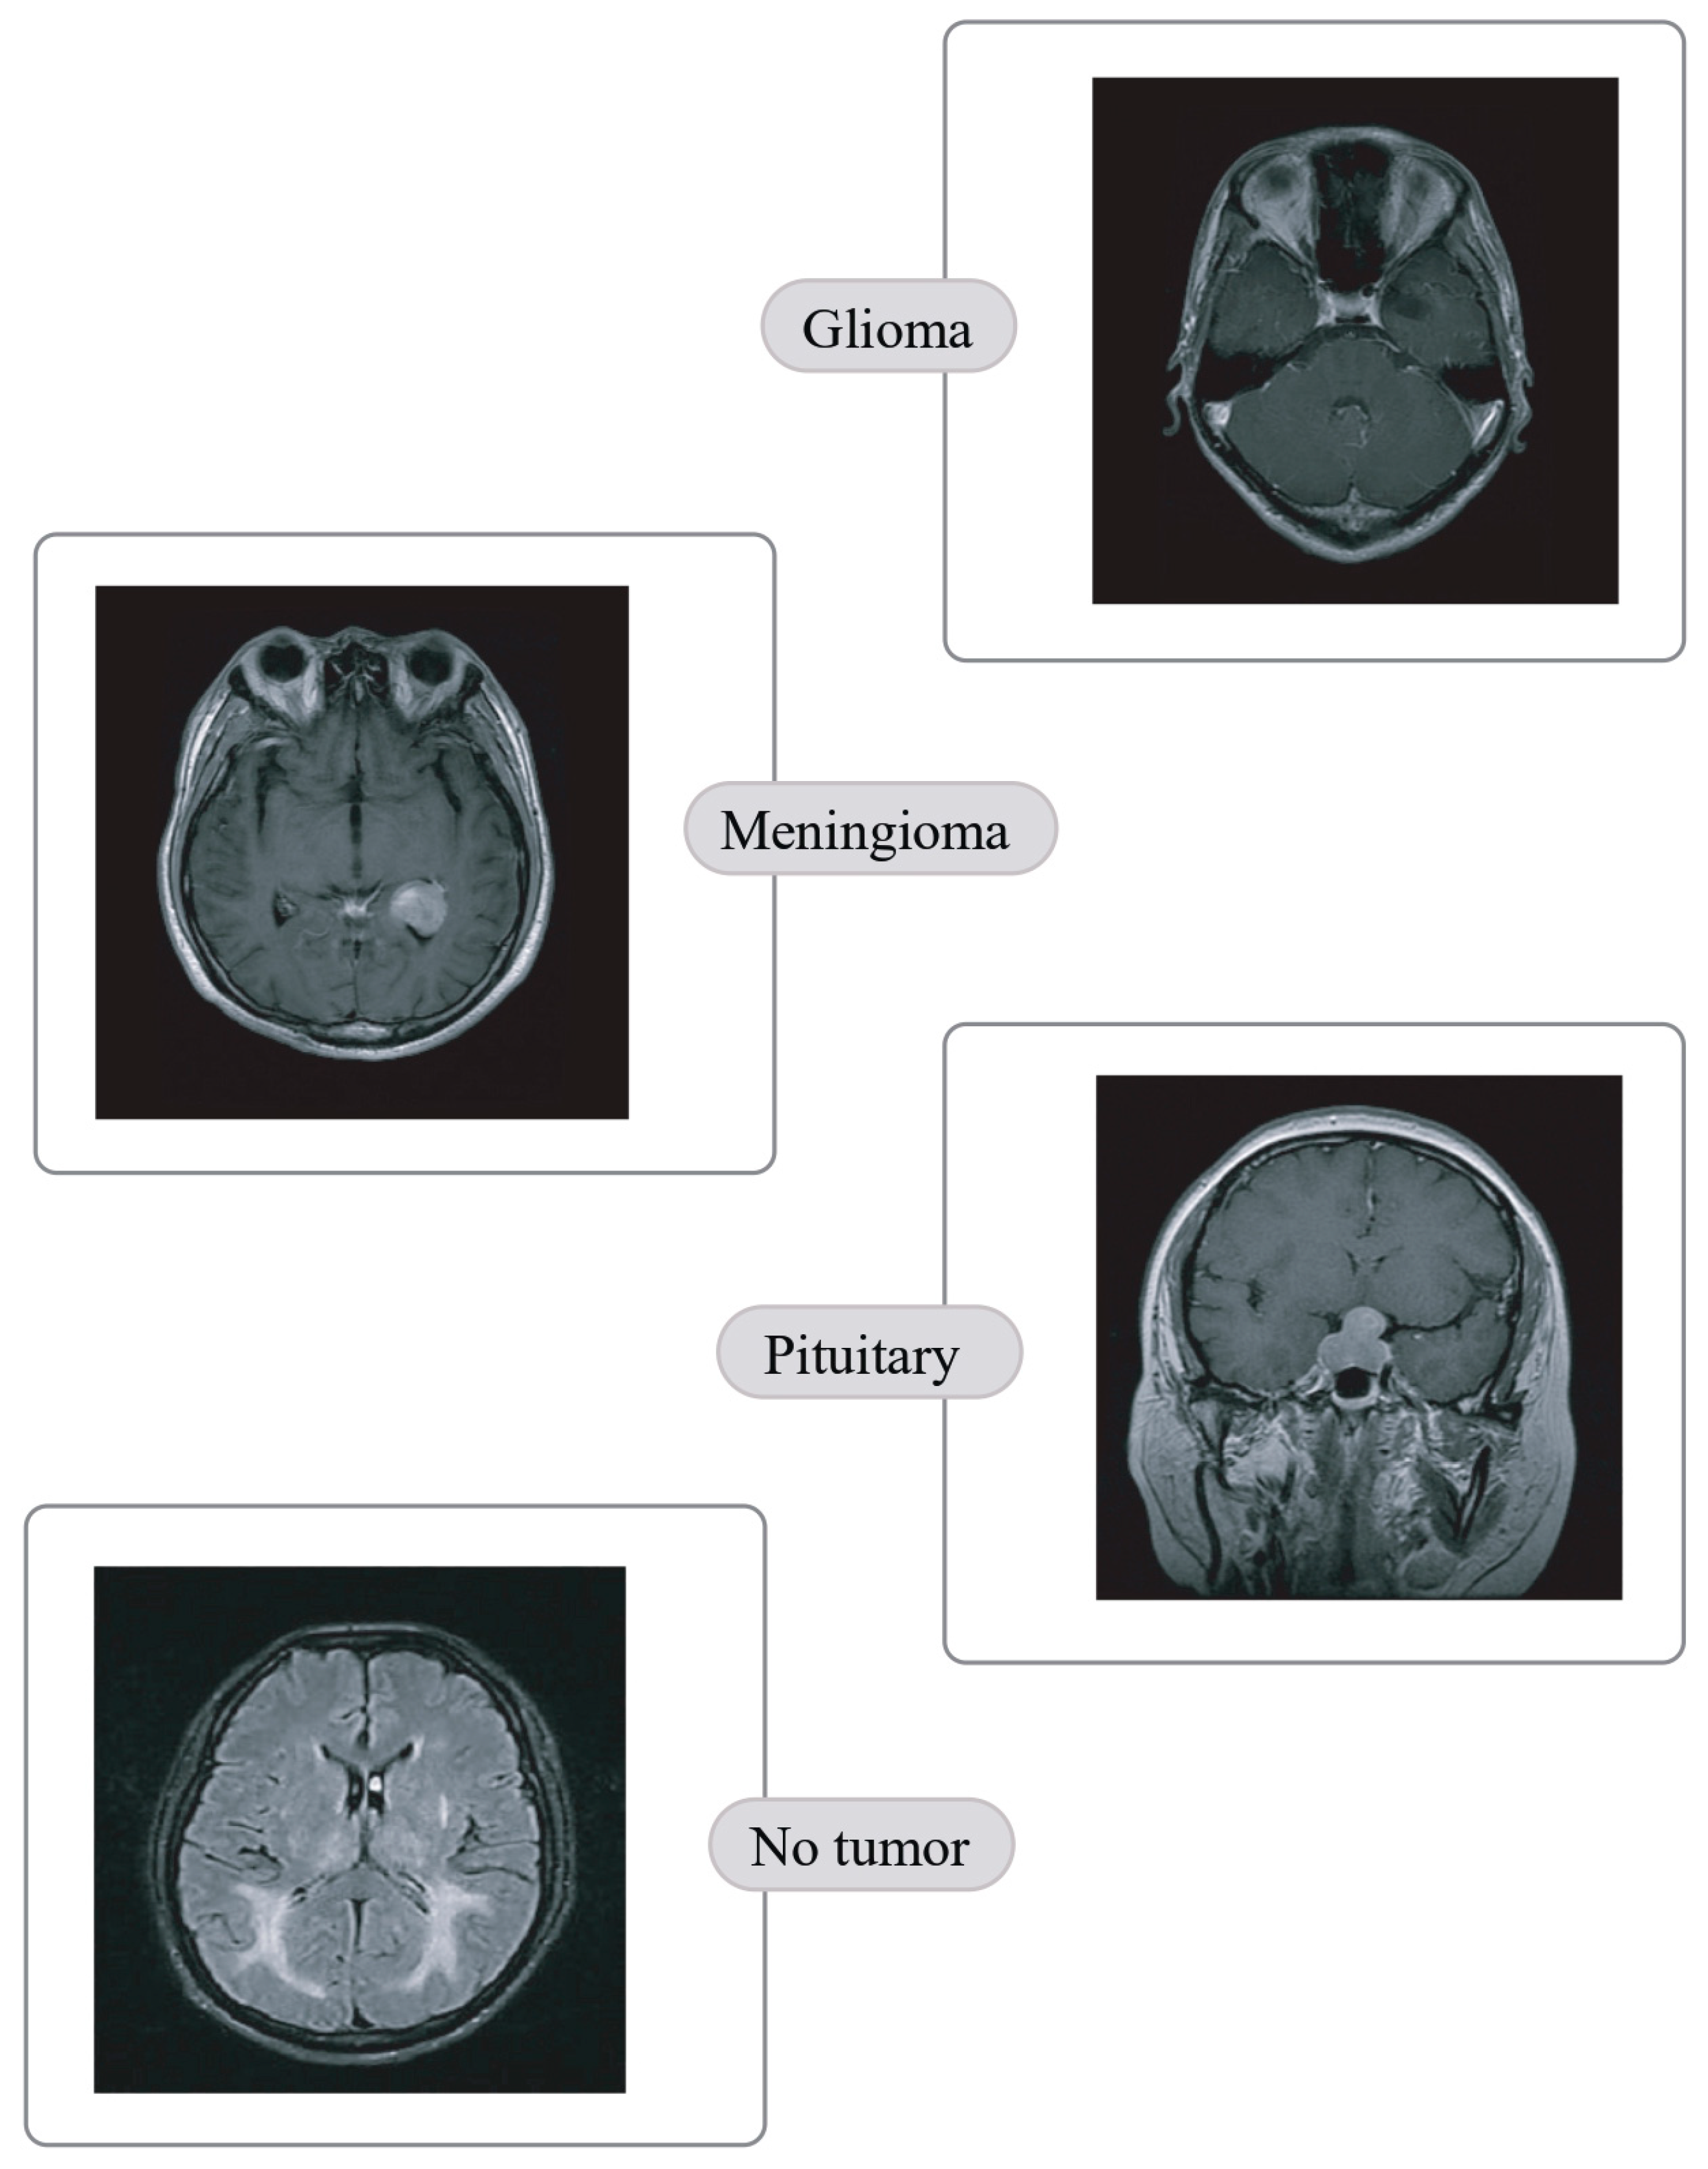

- Quaternary classification of MRIs into glioma, meningioma, pituitary and no tumor.

| Classes | Number of images | % |

|---|---|---|

| Pituitary | 300 | 22.88 |

| Meningioma | 306 | 23.34 |

| Glioma | 300 | 22.88 |

| No tumor | 405 | 30.89 |